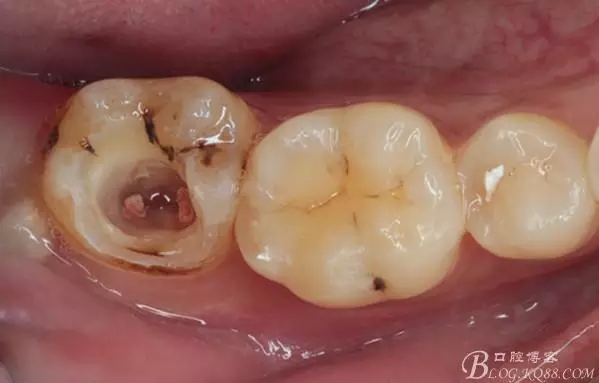

口腔檢查:37頰頜面齲洞,叩(+),探(+),冷熱測(cè)試與對(duì)照牙對(duì)比為敏感。17 27 47 均有不同程度齲壞,無明顯陽性體征。18 28 38 48 呈不同程度傾斜,38 48牙冠部分萌出。全口牙齒排列不整齊,口腔衛(wèi)生較差,牙石(++),部分牙齦發(fā)紅。X線檢查示37牙冠低密度影像累及牙髓,牙周間隙略增寬。

去除暫封物,拍照,比色。